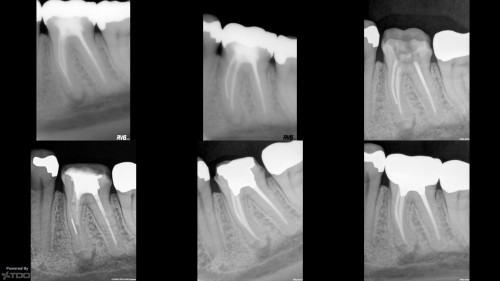

Core Only

By Kirk Huffaker / July 24, 2018

65 year-old female in good health.  Root canal treatment was completed by my predecessor 15 […]